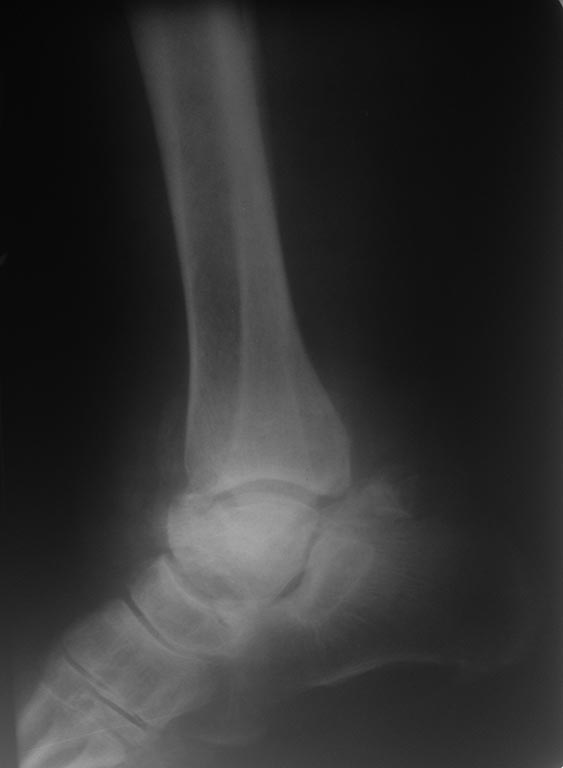

Перелом таранной кости. 56 лет женщина, подвернула правую стопу 06.07.15 не придала этому значения, продолжала ходить.

Постепенно стали усиливаться боли и деформация. 08.07.15 обратилась в поликлинику, больной сделан рентген . Из анамнеза страдает сахарный диабетом с 2002 года, онкопатологию отрицает. Хотелось бы узнать, уважаемые коллеги, о тактике лечения данной пациентки.

Такой переломо-вывих мог не беспокоить разве что при выраженной диабетической полинейропатии. Прогноз скверный. Вероятен исход в стопу Шарко.

Здравствуйте. Для принятия решения хорошо было бы получить рентгенограммы в проекции Mortise и Canale, лучше дополнить КТ-исследованием. Если возможно, выложите, пожалуйста и внешний вид стопы (фото).

Думали об КТ. Но выполнить КТ исследование затруднительно, вес больной около 130 кг, рентгенологи не одобряют. Мы не стали терять время и 10.07.15г. выполнили операцию: закрытая репозиция переломо - вывиха таранной кости. ЗЧКДО апп. Илизарова правой голени и стопы.